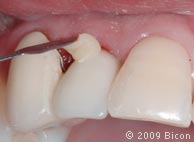

26. Для раскрытия верхнего бокового правого резца сделан надрез.

27. Извлечение заглушки с помощью специального инструмента.